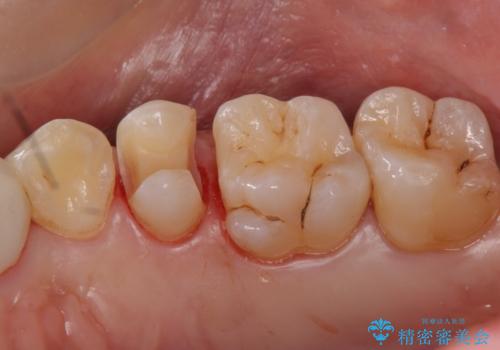

銀の詰め物を白くしたい セラミックインレーでの治療

セラミックインレーで治療を行いました。

- 左上5 セラミックインレー 77,000円費用は治療当時の料金となります

口の中にチラつく銀歯は適合の良いセラミックインレーでやり替えることで綺麗にやり替えることができます。